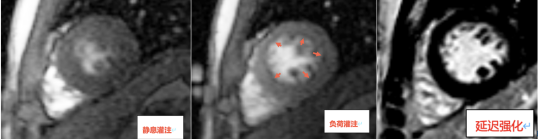

检查发现患者静息灌注未见异常(图1A),负荷灌注其左心室多节段可见心内膜下灌注缺损(图1B),延迟强化未见异常(图1C),提示患者心肌存在微循环障碍,这也解释了患者心外膜冠状动脉主要分支未见明显狭窄,仍反复出现胸闷心悸等症状的原因。小陈有糖尿病及高血压基础病,导致心肌微循环障碍,故治疗上予改善心肌微循环。